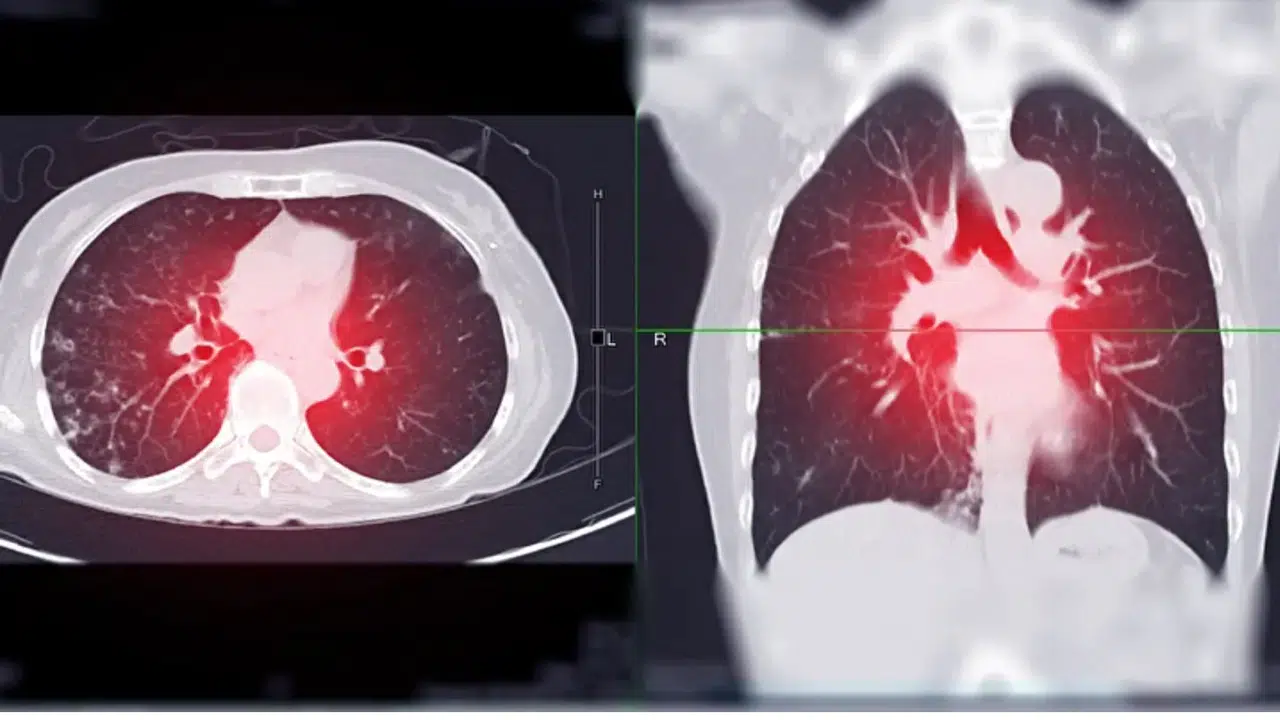

Uzmanlar, özellikle 50 ile 80 yaş arasındaki, uzun yıllar sigara kullanmış bireylerin düşük doz bilgisayarlı tomografi (BT) taramasına girmelerinin erken teşhis için hayati önem taşıdığını vurguluyor. Bu yöntemle erken evrede tespit edilen akciğer kanseri vakalarında sağkalım oranı yüzde 60 ile 90 arasında değişiyor.